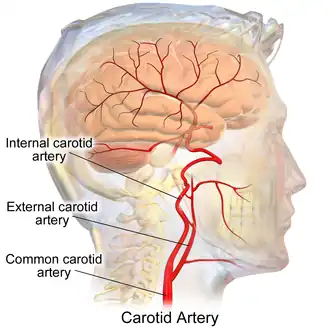

In anatomy, the left and right common carotid arteries (carotids) (English: /kəˈrɒtɪd/[1][2]) are arteries that supply the head and neck with oxygenated blood; they divide in the neck to form the external and internal carotid arteries.[3][4]

At approximately the level of the fourth cervical vertebra, the common carotid artery splits ("bifurcates" in literature) into an internal carotid artery (ICA) and an external carotid artery (ECA). While both branches travel upward, the internal carotid takes a deeper (more internal) path, eventually travelling up into the skull to supply the brain. The external carotid artery travels more closely to the surface, and sends off numerous branches that supply the neck and face.

The chief communications outside the skull take place between the superior and inferior thyroid arteries, and the deep cervical artery and the descending branch of the occipital artery; the vertebral artery takes the place of the internal carotid artery within the cranium.